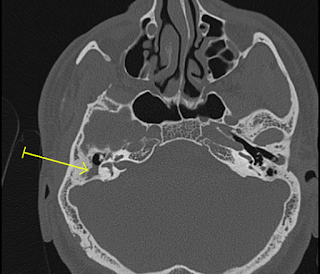

Normal cellular patterns are lost in Rt mastoid with collection in middle ear cavity. Right tympanic membrane is thickened and retracted.